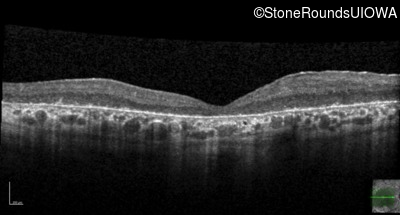

Optical Coherence Tomography - Right - 20/300 sc

Exemplar / OCT Stack

OCT Stack